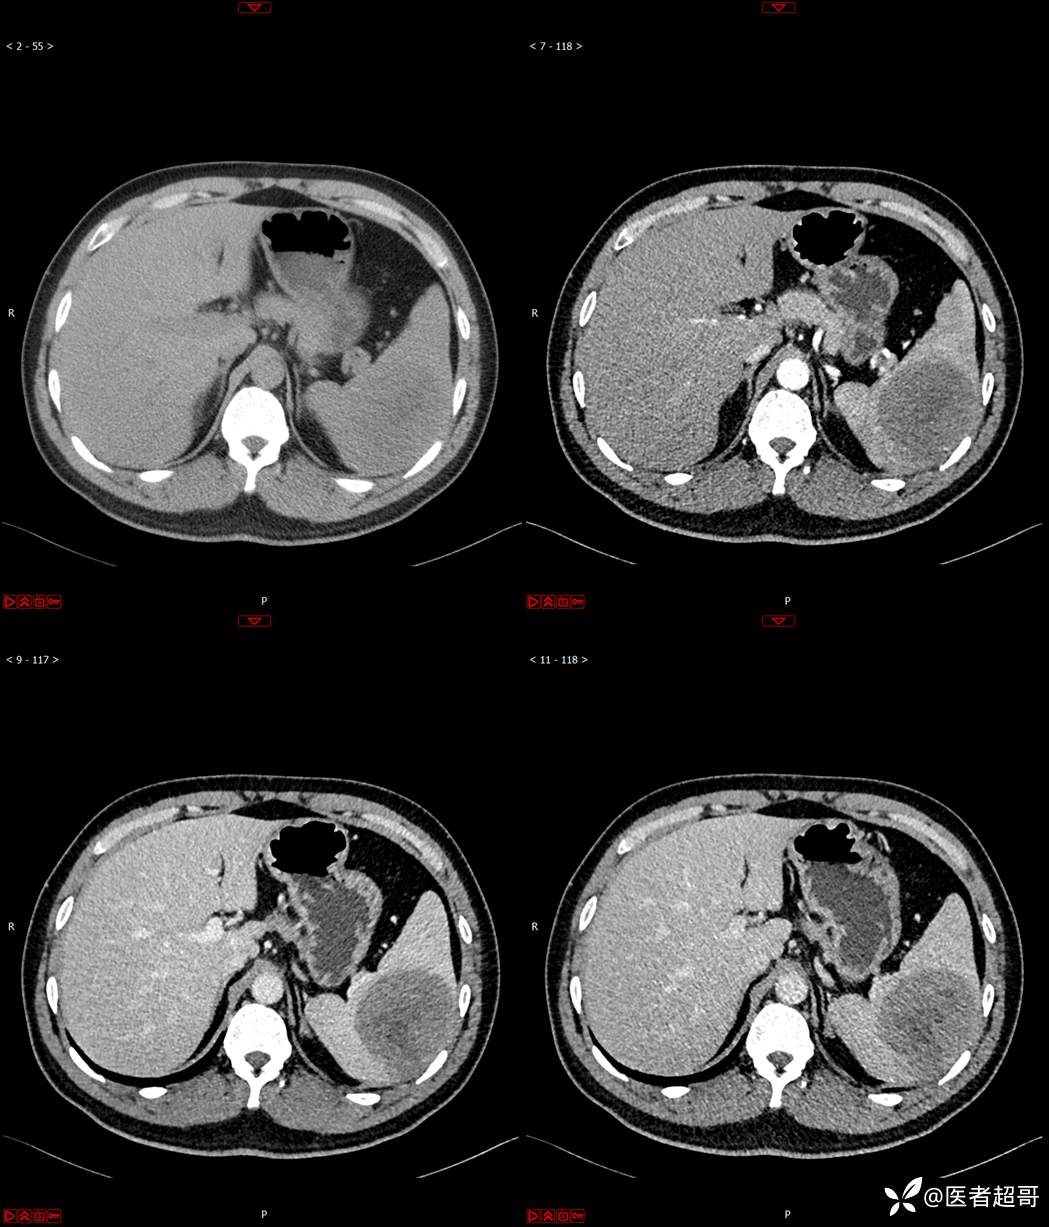

【影诊笔记596】脾脏占位01,你的病谱能网住吗?请分析,留言查询病理及术程!

主 诉:发现脾占位2月余。

现病史:患者2月余前体检彩超提示脾占位性病变,未予特殊诊治,2023.12.1于潍坊市坊子区人民医院行肝胆胰脾MR平扫提示脾脏占位性病变,左肾小囊肿,现患者无腹胀、腹泻,无恶心呕吐,无胸闷憋气等症状,今为求进一步治疗,患者来我院就诊,门诊以“脾占位性病变”收入院。患者自发病以来,一般情况可,神志清,精神可,饮食、二便正常,睡眠可,体重体力无明显改变。